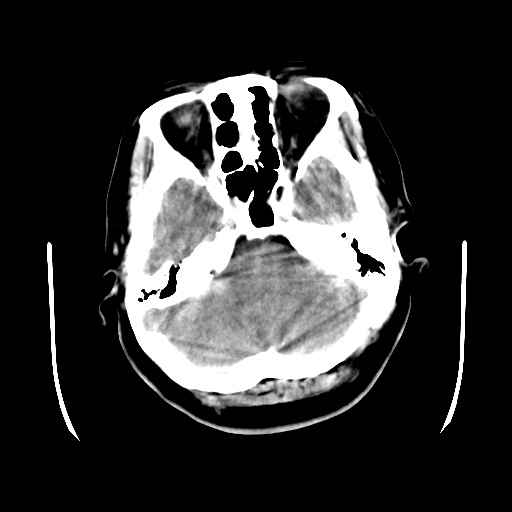

以下是引用cgf在2010-1-3 17:53:00的发言:[br]此病例多考虑:透明隔发育异常 透明隔囊肿可能性大;右侧基底节区(尾状核头)小片状低密度影考虑陈旧性腔梗[br][br]透明隔发育异常:包括透明隔间腔(第五脑室)、韦氏腔(第六脑室)、透明隔囊肿、透明隔缺如;前两者属于正常变异,后两者属于发育畸形;[br]透明隔间腔向下扩张形成韦氏腔;[br]有时透明隔间腔与透明隔囊肿很难鉴别;透明隔间腔间距一般不超过0.5cm,间距大于0.5cm时应考虑透明隔囊肿;[br]透明隔缺如为两侧脑室间隔缺如、融合成单脑室畸形,可伴有智力发育异常;[br][br]

以下是引用liaoqiang在2010-1-3 16:04:00的发言:[br]考虑侧脑室脉络丛囊肿?不除外变异的威氏腔。

以下是引用江广1996在2010-1-3 20:17:00的发言:[br]考虑变异的威氏腔。不除外侧脑室脉络丛囊肿.[br]透明隔囊肿大多数偏前,在侧脑室前角之间。